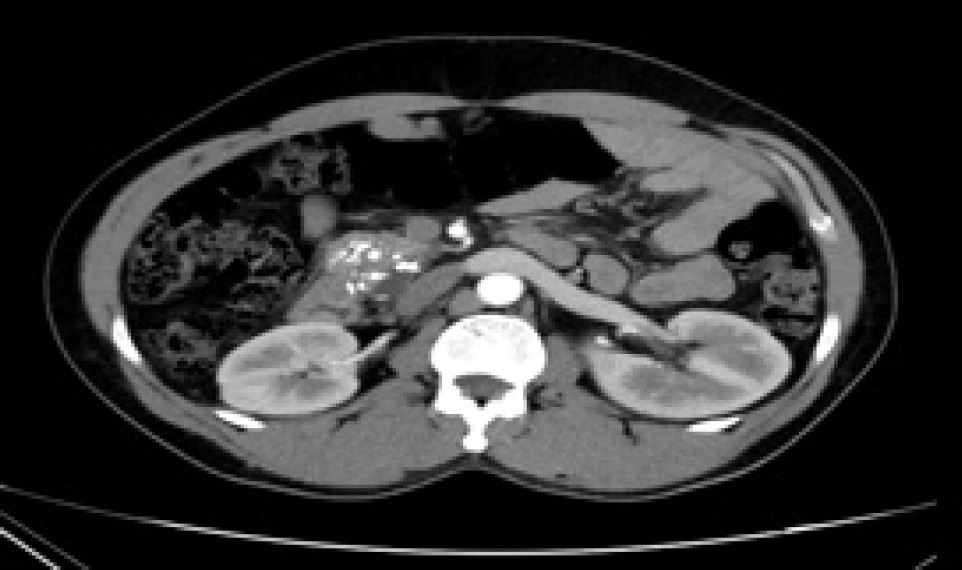

Figure 1: Ultrasound image of renal biopsy before ablation.

The growing issue of managing numerous small kidney masses, which exhibit unpredictable progression, within a population of uncertain lifespan, presents a challenging situation for medical professionals. This scenario has prompted the development of ablative methods. While the preferred approach, partial nephrectomy, may not be suitable for individuals with significant underlying health conditions and a high risk of anesthesia-related complications, ablative techniques have become noteworthy. These techniques offer several benefits, including the ability to be performed in an outpatient setting without the need for general anesthesia, which ultimately reduces the potential for complications. In our study, we followed the patients for the intermediate-term results post-ablation that is after a period of 3 years. Most of our patients were seen to have achieved almost complete resolution at the intermediate term on CT imaging (Figures 2 and 3). Our study showed that the mean age of patients undergoing ablation was 63.35 years. In a study by Johnson DB et al., the average patient age was 61.2 years (10). The majority of the patients had clear-cell RCC on histology (92.85%) and two patients had papillary carcinoma (7.14%). In a study done by Psutka SP et al., pathologic analysis of renal biopsies demonstrated that tumors were of the clear cell variant in 97 (54.1%), papillary in 33 (17.4%), chromophobe in 4 (2.2%), an oncocytic variant of RCC in 5 (2.7%), and RCC, not otherwise specified histologic type, in 46 (24.9%) (11). In our study, there was no significant effect on renal function pre- and post-ablation. In a study done by David Curry et al., 19 (24%) patients had a subsequent deterioration in eGFR with a median change of 7 (IQR [interquartile range]: 5–11). Renal function deterioration was seen significantly more frequently and at a significantly greater level in the cohort of patients with pre-existing renal impairment (P < 0.005/P = 0.001). No significant difference in the number affected or level of deterioration was seen for gender (P = 0.1/P = 0.069), diabetes (P = 1.0/P > 0.99), hypertension (P = 0.296/P = 0.213), or vascular disease (P = 1.0/P = 0.14) (4). In a study by Lucas SM et al., a GFR decrease of less than 45 mL per minute per 1.73 m2 was noted in 3 of 63 patients in the RFA group, 3 of 55 in the partial nephrectomy group, and 11 out of 40 in the radical nephrectomy group (P 0.001) (12).

Figure 2: Pre-ablation computerized tomography (CT) scan showing a small renal mass in the mid-pole of the right side kidney.

Figure 3: Computerized tomography (CT) scan after 3-year follow-up showing almost complete resolution of the mid-polar small renal mass in the right kidney.